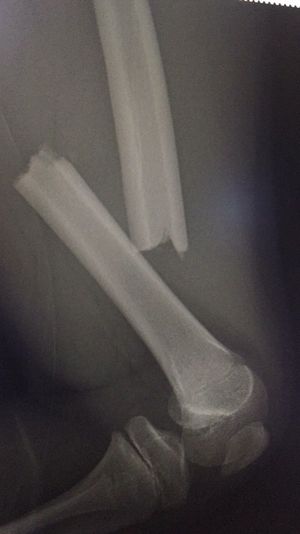

Snapped Femur

Peds pt came into the ER after a bike accident. Whats next?

Not forget to think about child abuse. Diaphyse fracture of the femur is suspectable for child abuse (epiphyseal plate is not closed jet).